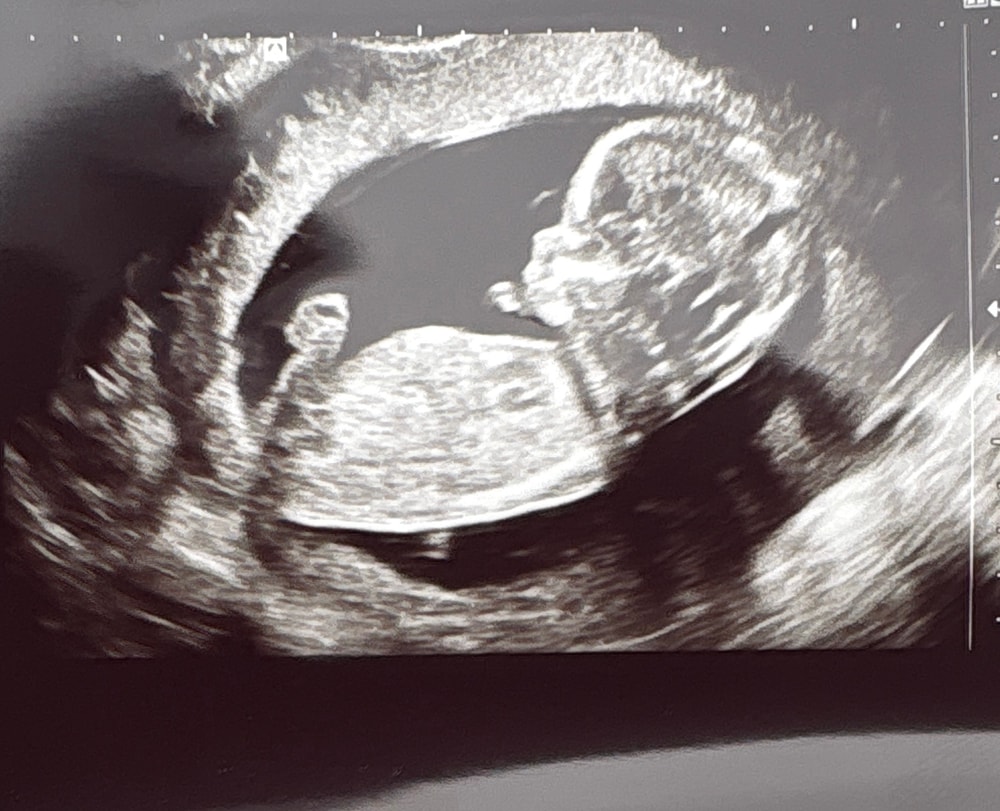

Первый скрининг. 💙

Всё о нашей беременностиНаконец то настал день первого скрининга. По узи все отлично. Срок сегодня 13.1

очень рада, что в ЖК мне дали чудесное фото😍😍 наше чудо 💙